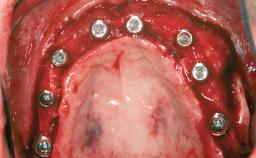

A 46-year-old woman was referred for treatment whose main complaints were mobility of her fixed partial dentures (right maxilla and left mandible) and periodontal bleeding during function. She also reported having taken systemic antibiotics to treat recurrent swelling in the area of the upper left molars. The patient had not seen a dentist for at least 2 years. She did not smoke and had no history of major systemic disease other than two minor orthopedic procedures some years back. The first-visit examination revealed poor plaque control, tooth mobility, periodontal disease, and a residual dentition widely associated with deep periodontal pockets.

Bone Augmentation Horizontal|Staged|Vertical

Augmentation Materials Autogenous chips|Autogenous block(s)|Xenogenous

Bone Volume Deficient vertically or deficient vertically AND horizontally